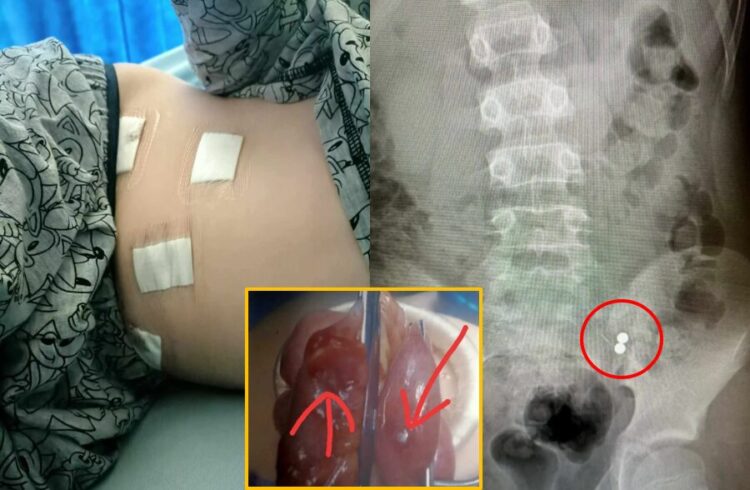

영국 매체 더선의 보도에 의하면, 허트포드셔에 사는 바비는 두 개의 작은 자석 볼을 삼킨 후 응급실을 찾았다. 바비의 엄마인 해나 아메르(38)는 “바비가 초코과자처럼 자석 볼을 공중으로 던졌다가 입으로 받았는데, 크기가 너무 작아 곧장 목으로 넘어가버렸다”며 사건이 일어난 당시 상황을 설명했다. 응급실로 달려가 엑스레이를 찍어보니 하나는 가슴에 하나는 장에 있는 것으로 확인됐는데, 의사는 하나가 먼저 나오면 괜찮을 거라며 강력한 완하제를 처방했다.

병원에 5일간 입원해 음식도 먹지 못한 채 지냈지만, 자석은 끝내 나오지 않았다. 결국 아메르는 CT 검사를 요구했고, 검사 결과 두 개의 자석이 장에서 서로 뭉쳐 있는 것이 확인되어 바비는 급히 수술을 받게 됐다. 아메르는 “의사는 조금만 시간을 더 끌었더라면 아이의 장에 구멍이 났을 거라고 했다”며 “아이는 장루 주머니를 달 수도 있었다”고 설명했다.